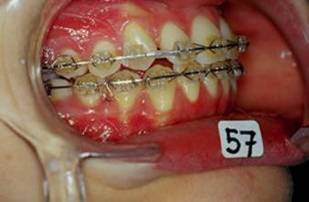

Collage bas fait presque 3 mois apres le haut, avec des elastiques verticaux pendant 3 semaines seulement. Et voici les photos, la suite je vous en passe car il s'agit de simple finition.

P.S. photos au moment du collage bas

En realite les choses etaint deja dans le bon sens des le RDV du collage mandibulaire, si vous regarder les photos 13 et 14, la beance etait deja presque fermee, les elastiques etaient pour eviter que cela ne recidive. Donc le but n'etait pas d'egresser les dents pour fermer la beance mais plutot empecher les deux arcs de s'eloigner.

Comme je l'ai dit, je les ai utilise pendant 3 semaines seulement au moment du collage du bas, apres rien. Les dernieres photos sont presque 3 mois apres le collage du bas et l'arret des elastiques et la beance n'a pas recidive.